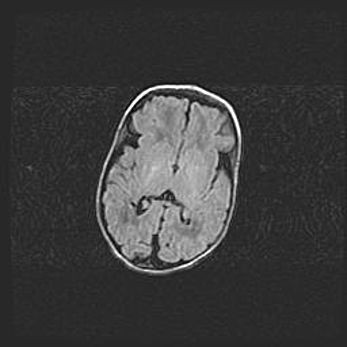

Церебральная ишемия II.

Возраст: 5 дней

Вес: 3400 г

Пол: женский

Окружность головы: 35 см

Срок гестации: 39 недель

Церебральная ишемия – это заболевание, характеризующееся недостаточностью (гипоксией) либо полным прекращением (аноксией) снабжения мозга кислородом по причине закупорки одного или нескольких сосудов. Это приводит к  что метаболическим расстройствам различной степени тяжести в тканях головного мозга, развитию коагуляционных некрозов и гибели нейронов.